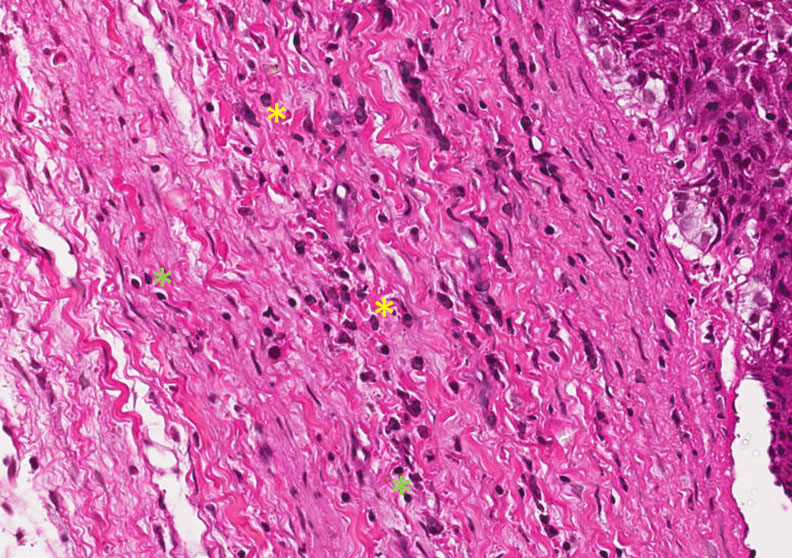

Tecido conjuntivo denso exibindo uma resposta crônica com infiltrado inflamatório predominantemente de linfócitos (asterisco amarelo) e plasmócitos (asterisco verde), vasos de neoformação (setas amarelas) e fibras colágenas. .

Descrição